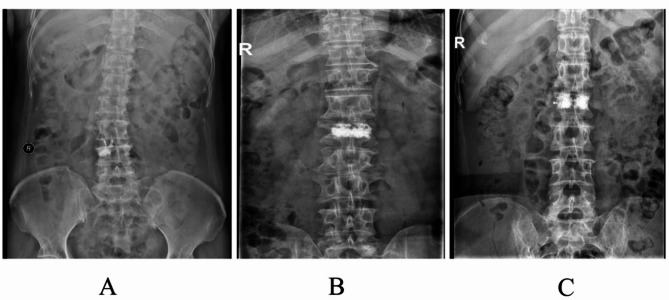

Results: There were no significant differences in baseline characteristics between the two groups, indicating comparability (P > 0.05). All surgeries were completed successfully without complications such as nerve injury or pedicle fracture. No significant differences were found between the groups in terms of operative time, intraoperative bleeding, or radiation frequency (P > 0.05). However, the amount of bone cement injected was significantly greater in the TPPA group compared to the CTPA group (P < 0.05). At 1 day postoperatively, the VAS score and ODI in the TPPA group were significantly lower than those in the CTPA group (P < 0.05), indicating better immediate pain relief and function. No significant differences in VAS or ODI were observed between the groups at preoperative, 3-month, 6-month, or 12-month time points (P > 0.05). Both VAS and ODI scores showed steady improvement within each group, with significant differences between all consecutive time points (P < 0.05). The Beck Index at both 1 day and 12 months postoperatively was significantly higher in the TPPA group compared to the CTPA group (P < 0.05). Within-group comparisons also showed significant improvement in the Beck Index at both postoperative time points compared with preoperative values (P < 0.05). Additionally, the TPPA group demonstrated a significantly higher rate of satisfactory bone cement distribution than the CTPA group (P < 0.05).

Conclusions: In the treatment of OVCF with PKP, the TPPA demonstrated comparable surgical safety to the CTPA. However, TPPA offered advantages in achieving better bone cement distribution, more effective immediate postoperative pain relief, and superior restoration and maintenance of the height of the injured vertebral body.